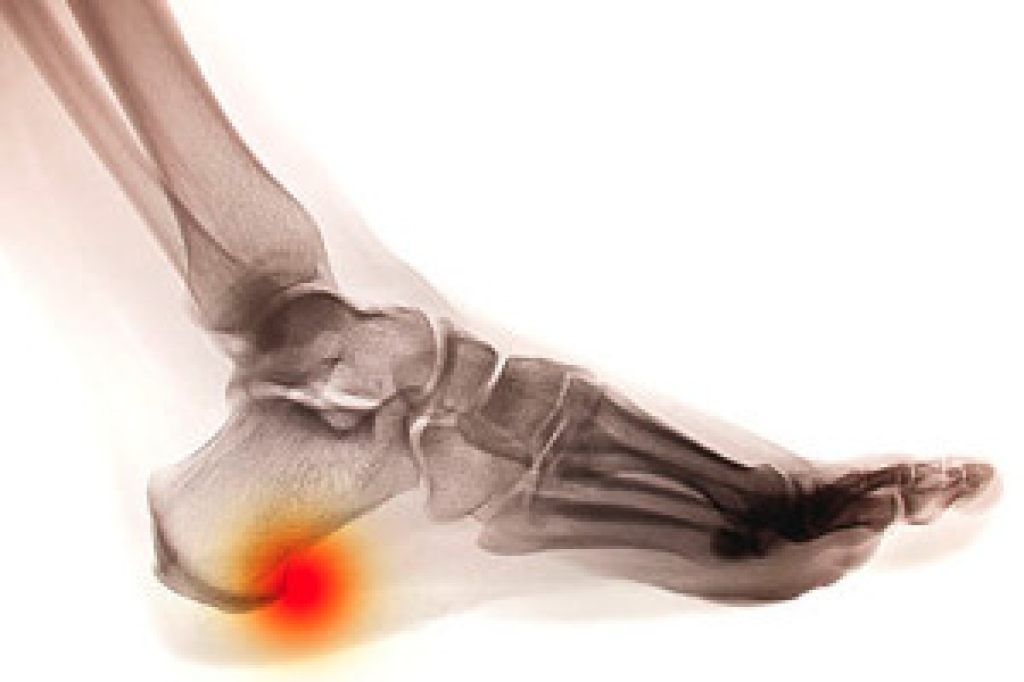

To figure out the cause of foot pain, podiatrists utilize several different methods. This can range from simple visual inspections and sensation tests to X-rays and MRI scans. Prior medical history, family medical history, and any recent physical traumatic events will all be taken into consideration for a proper diagnosis.

Can Heel Spurs Be Prevented?

Many people have heel pain and show no other symptoms. This can indicate a heel spur has developed, and treatment is often sought for relief. A heel spur is defined as a bony growth that gradually forms on the bottom of the heel, and can come from excessive pressure the heels endure from being overweight, or if the plantar fascia becomes damaged. Wearing shoes that do not fit correctly may cause a heel spur to develop, in addition to having an abnormal foot structure. There are specific groups of people who may be prone to developing a heel spur. These can include runners, elderly people, diabetic patients, or people who have frequent gout attacks. People who have pain with a heel spur often notice there is tenderness surrounding the heel, and the affected foot and ankle may become swollen. Additionally, there may be sharp heel pain after rising in the morning. Effective prevention methods may consist of stretching the feet regularly, wearing insoles that can provide support, and maintaining a healthy weight. If you feel you have a heel spur, it is strongly urged that you consult with a podiatrist who can properly treat this condition.

Heel spurs are formed by calcium deposits on the back of the foot where the heel is. This can also be caused by small fragments of bone breaking off one section of the foot, attaching onto the back of the foot. Heel spurs can also be bone growth on the back of the foot and may grow in the direction of the arch of the foot.

Pain

The pain associated with spurs is often because of weight placed on the feet. When someone is walking, their entire weight is concentrated on the feet. Bone spurs then have the tendency to affect other bones and tissues around the foot. As the pain continues, the feet will become tender and sensitive over time.